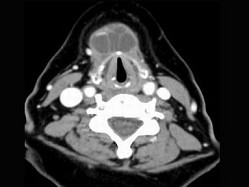

3.女,57岁,颈部不适,CT如图所示,应诊断为 ( )![]() ![]() ![]() ![]() |

| 正确答案:C |